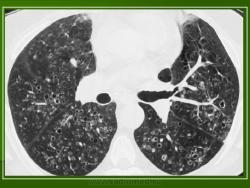

Изучение скелетограмм у 27 из 29 больных позволило выявить изменения, подтвердившие диагноз данного заболевания. Это указывает на высокую диагностическую ценность рентгенологического обследования при ГКЛ. Наиболее часто определялись поражения черепа в виде множественных (24) или единичных (3) дефектов в костях свода, где четко прослеживалась «штампованность» очагов. Дефекты не содержали секвестров, имели различную форму, величину, четкие наружные и неровные, фестончатые внутренние контуры. Периостальная реакция отсутствовала. При множественных участках деструкций картина напоминала «географический или ландкартообразный» череп, или «изъеденную молью ткань» (Рис.1).

В 5 наблюдениях (21%) из больных с распространенной формой заболевания отмечались изменения в легких в виде обогащения, избыточности легочного рисунка, его деформации по сетчато-петлистому типу, очаговых теней. Корневая и медиастинальная аденопатия отсутствовали. В 1 случае в легких выявлена киста, которая периодически осложнялась нагноением (Рис. 4).

Поражение легочной ткани (рис. 22) свойственно любому возрасту. Часто больные имеют общие симптомы — лихорадку, слабость, реже — кашель, одышку, боли в грудной клетке. На рентгенограммах отмечается деформация и усиление легочного рисунка и микроузловые инфильтративные тени. Поражение костного мозга (с наличием клеток Лангерганса) сопровождается цитопенией периферической крови.

Рис. 22. Поражение легких при Лангер-гансово-клеточном гистиоцитозе.